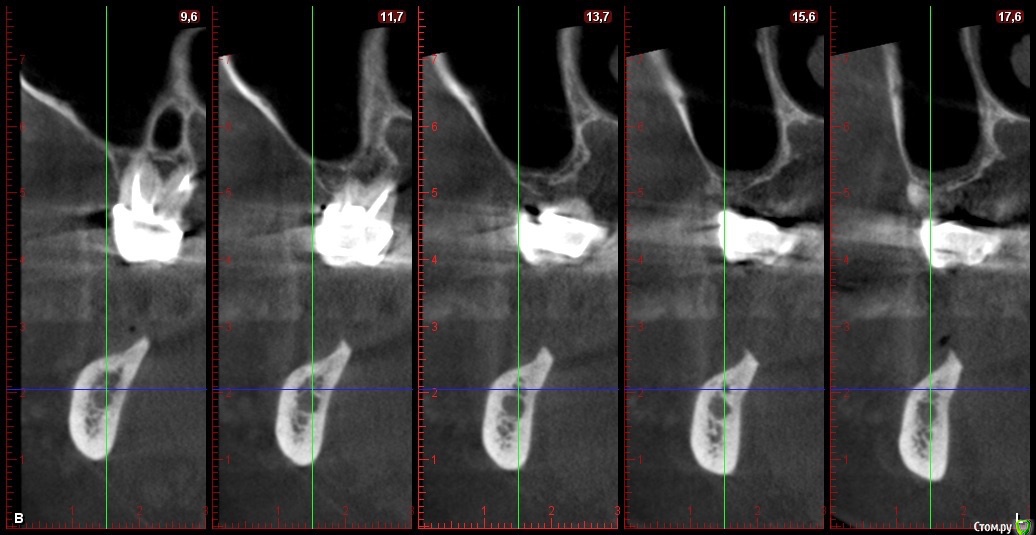

Глеб Митрофанов Опубликовано 22 октября, 2015 Автор Поделиться Опубликовано 22 октября, 2015 Срезы кт Ссылка на комментарий

basha.ru Опубликовано 23 октября, 2015 Поделиться Опубликовано 23 октября, 2015 Спасибо за кейс.Скажите пожалуйста какая высота кости до нижнечелюстного канала?Спасибо. Ссылка на комментарий

Глеб Митрофанов Опубликовано 23 октября, 2015 Автор Поделиться Опубликовано 23 октября, 2015 (изменено) Спасибо за кейс.Скажите пожалуйста какая высота кости до нижнечелюстного канала?Спасибо.До канала , в самой низшей точке - 4,5-5 мм Изменено 23 октября, 2015 пользователем Глеб Митрофанов Ссылка на комментарий